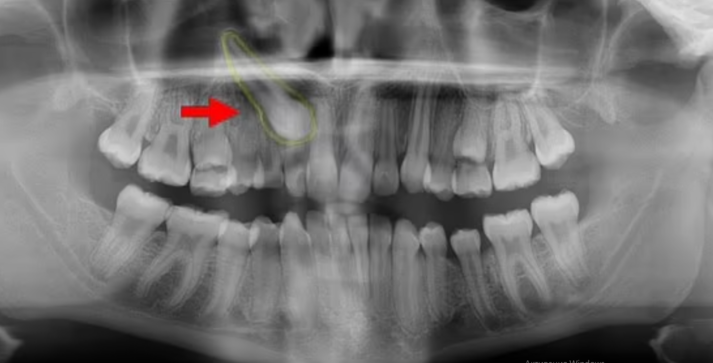

У Нью-Йорку в 38-річного чоловіка медики виявили справжній зуб у носі. Стаття про це з'явилася в науковому журналі The New England Journal of Medicine, пише Mail Online.

Чоловік скаржився, що кілька років має проблеми з диханням через праву ніздрю. Провівши риноскопію за допомогою камери та ліхтарика, лікарі виявили в носі «тверду безболісну білу масу». З'ясувалося, що це 14-міліметровий ектопічний зуб.

Чоловікові зробили успішну операцію і видалили зуб. Через три місяці проблеми з диханням припинилися.